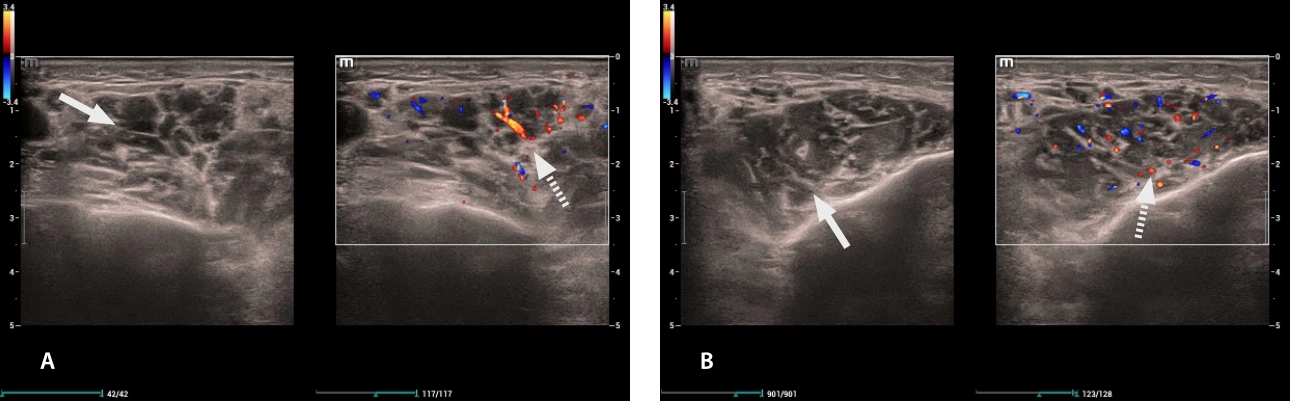

Fig. 2. Submandibular glands: (A) right, (B) left. Both were presented with hypoechogenic images in their entire extension (white arrow), with vascularity preserved on color Doppler/Power Doppler (dashed arrow)).

lymphoma-simulator-fig3-pc

Fig. 3. Parotid glands: (A) right, (B) left. Both were presented with hypoechogenic images (white arrow), with vascularity preserved on color Doppler/Power Doppler (dashed arrow).

lymphoma-simulator-fig4-pc